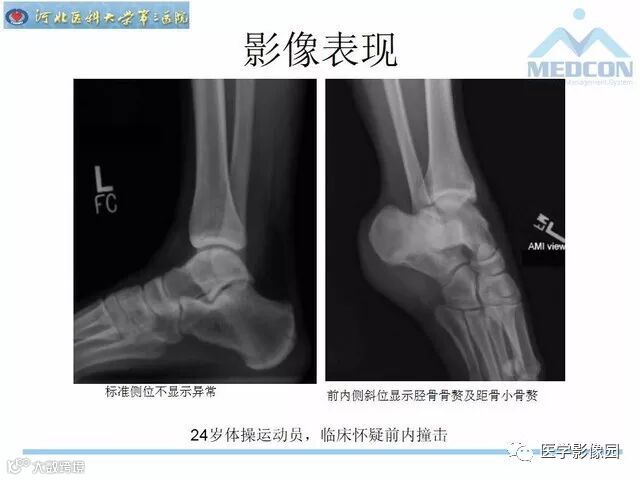

踝关节撞击综合征影像诊断,干货满满,值得收藏!

导读:踝关节撞击综合征影像诊断。干货满满,值得收藏!

踝关节撞击综合征影像诊断。干货满满,值得收藏!